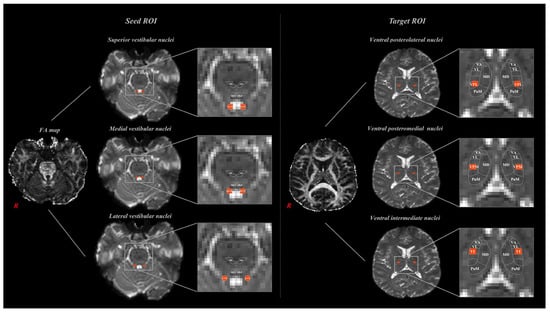

3. Results